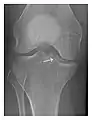

High-energy trauma fractures

Occult osseous injuries may result from a direct blow to the bone by compressive forces of adjacent bones against one another or by traction forces during an avulsion injury. Lesions in the tibial plateau, hip, ankle, and wrist are often missed. In a tibial plateau fracture, any disruption of the posterior and anterior cortical rims of the plateau should be sought. Impaction of subchondral bone will appear as an increased sclerosis of the subchondral bone (Figure 1). In the hip, posterior acetabular fractures also present subtle radiographic findings. The acetabular lines should then be carefully examined keeping in mind that the posterior rim, which is harder to see on X-rays, is more frequently fractured than the anterior rim (Figure 2). In the wrist, detection of carpal bone fractures is often challenging, with up to 18% of scaphoid fractures radiographically occult. Carpal fractures, especially the scaphoid, are associated with the risk of avascular necrosis. In apparently normal wrist radiographs from symptomatic patients, if there is history of a fall on an outstretched hand with pain in the anatomic snuffbox, suggesting scaphoid injury, the initial examination with posteroanterior, lateral, and pronation oblique views must be complemented by other specific views such as supination oblique and the "scaphoid" view A careful examination of cortices for evidence of discontinuity or offset and cancellous bone for lucency is necessary (Figure 3).[1]

c

Figure 3: A 26-year-old man presenting with wrist pain after being assaulted. (a) Initial anteroposterior radiograph shows a subtle linear lucency within the scaphoid extending to the scaphocapitate articular surface that was overlooked (arrow). (b) Initial "scaphoid" view was negative. (c) Followup anteroposterior radiographs, 12 days later, shows obvious scaphoid fracture (arrows).[1]